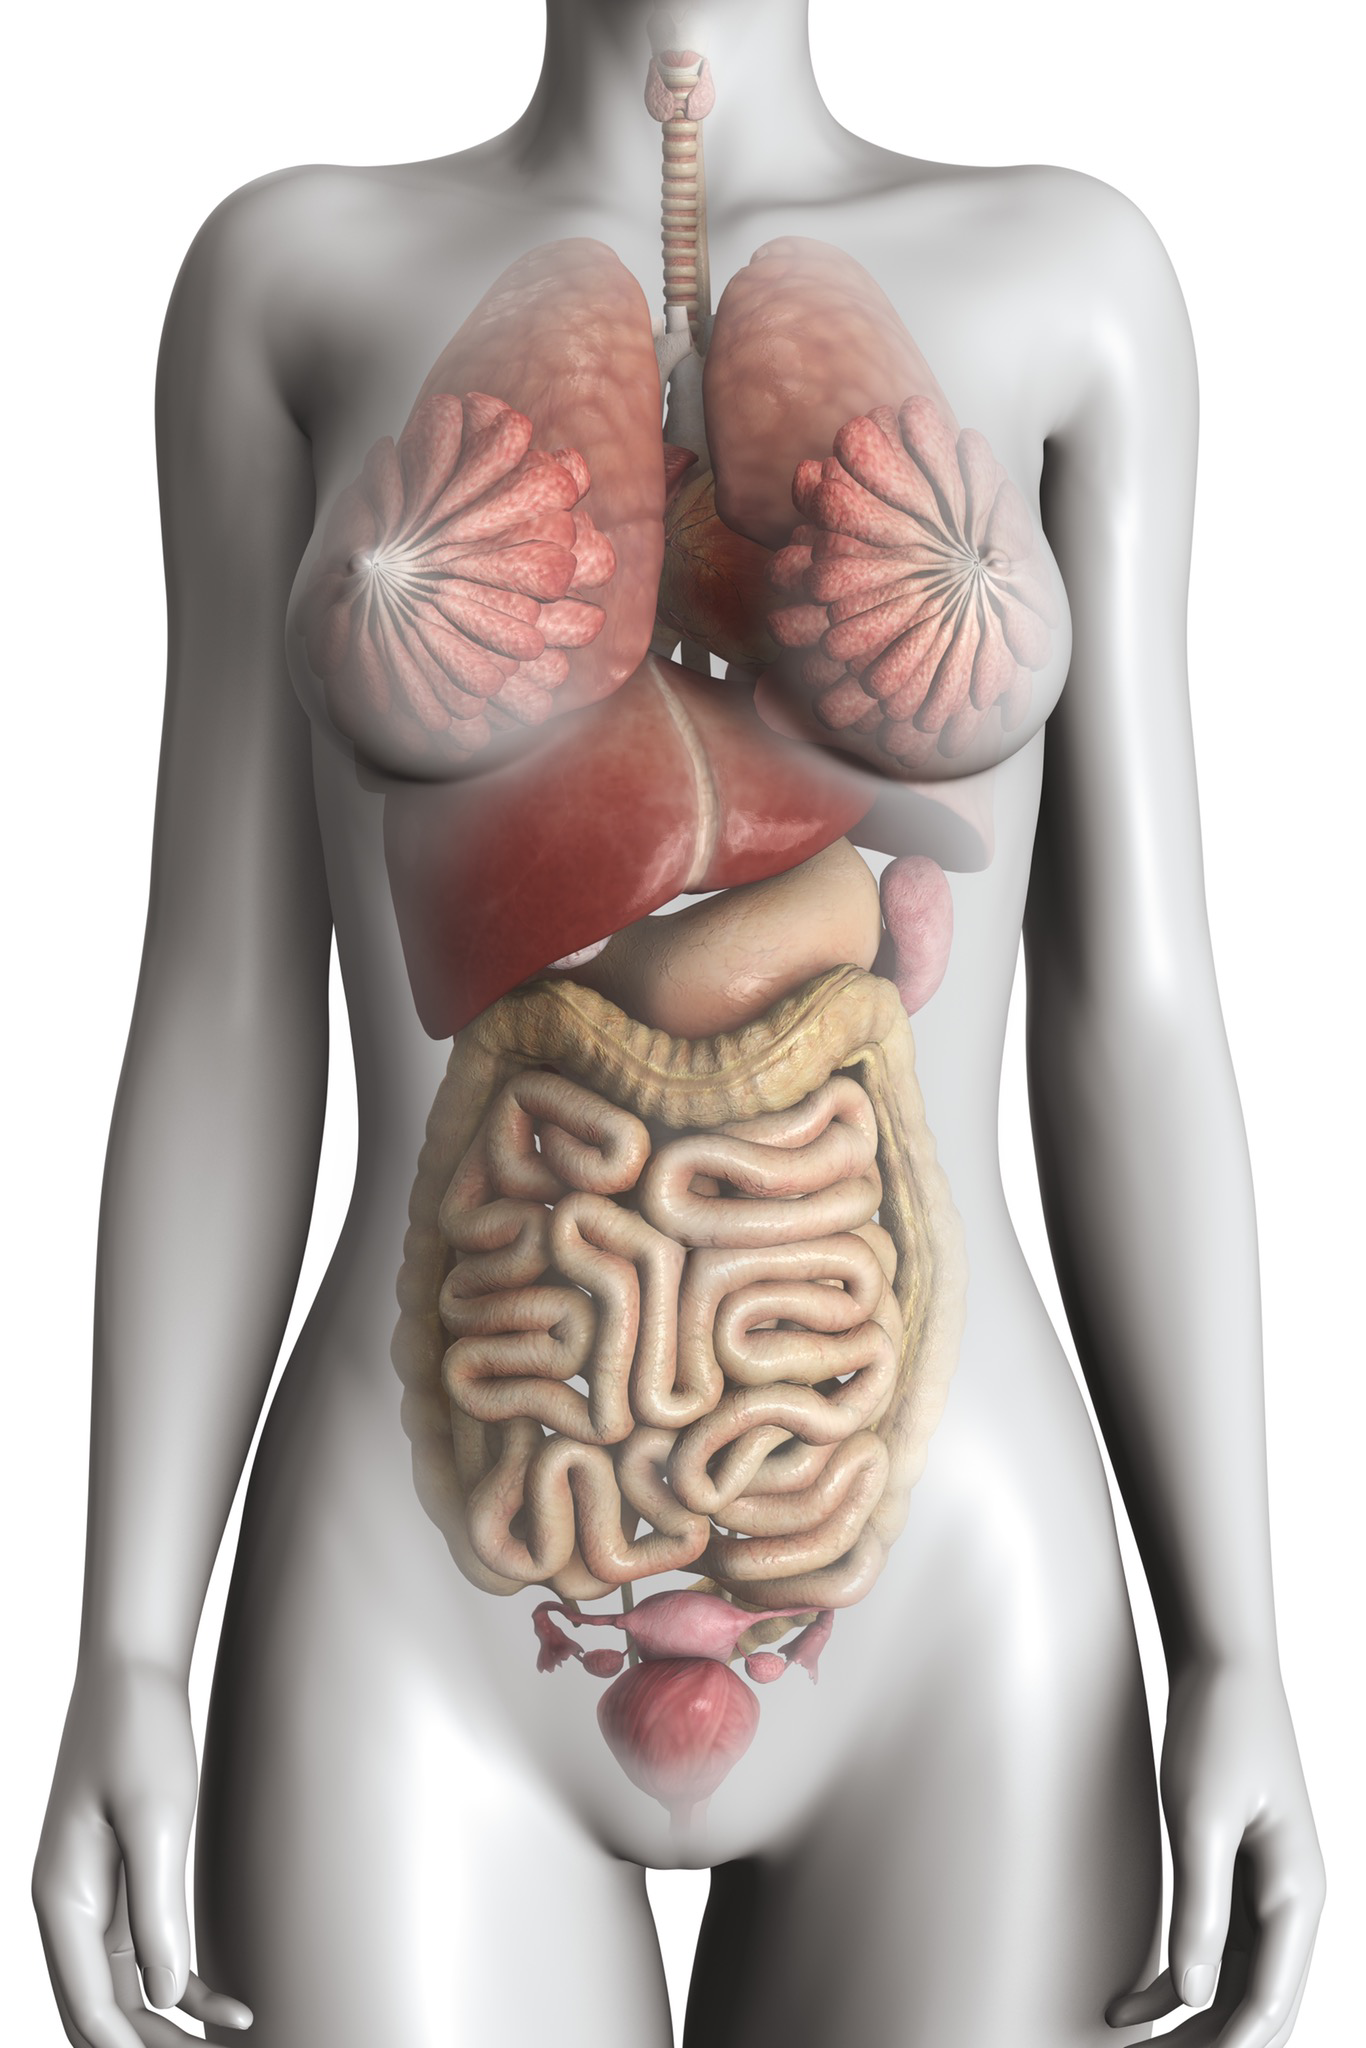

Изображения и визуализация внутренних органов человека